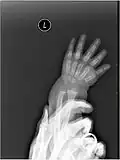

X-ray image of human infant left hand. -